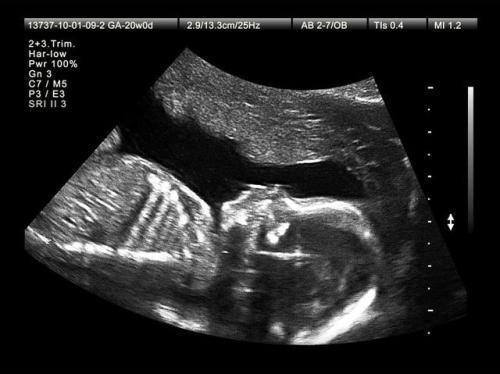

10、第十~十二次产检时间:孕38—40周每周一次项目:常规检查,胎心监护、胎位固定、胎头下降、做好生产准备。注意:不需要空腹,需要准备好自己要带的东西,比如档案卡、身份证、准生证、现金、充电器等,做好生产的一切准备。